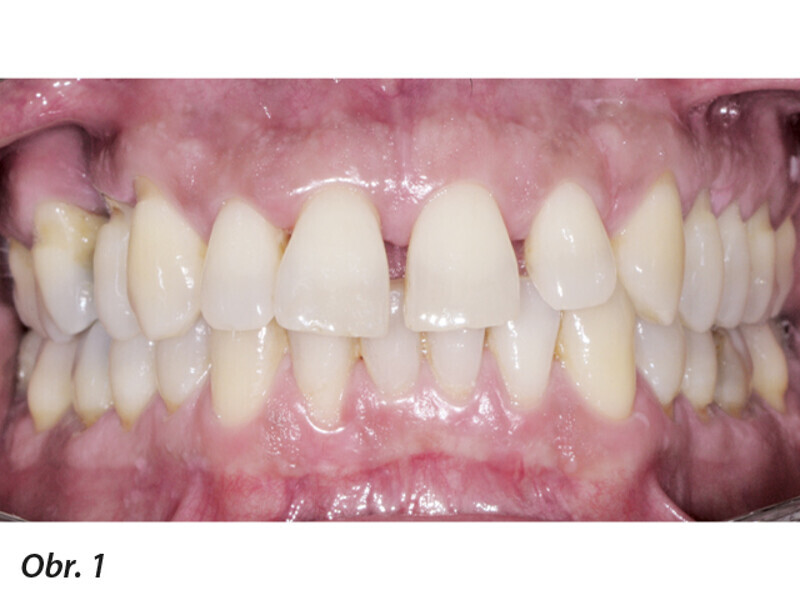

Multidisciplinární léčba u pacienta se závažnou parodontitidou